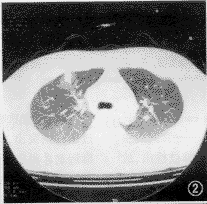

CT扫描,12例均有明显异常病灶显示。本组病例胸部CT表现包括:(1)小结节病灶 10例,结节影直径均在1 cm以下(范围0.5~1.0 cm),位居肺野外带胸膜下部(图1),其中8例小结节影周缘可见磨玻璃样密度的晕圈,即月晕征(图2,3)。(2)小斑片局灶性磨玻璃样密度影,在肺野外带浸润(图4),斑片与正常肺临界缘呈“小三角形”改变7例,部分在肺尖部散在,形似浸润型结核(图5)。(3)外带支气管血管束呈局灶性“Y”形增粗3例(图6)。上述小结节影、小斑片淡薄影均在两肺周边区域呈多灶性散在分布,没有大叶融合倾向。全组病例纵隔、肺门部未见肿大淋巴结。

图2 右上肺前段胸膜下区“小结节月晕征”